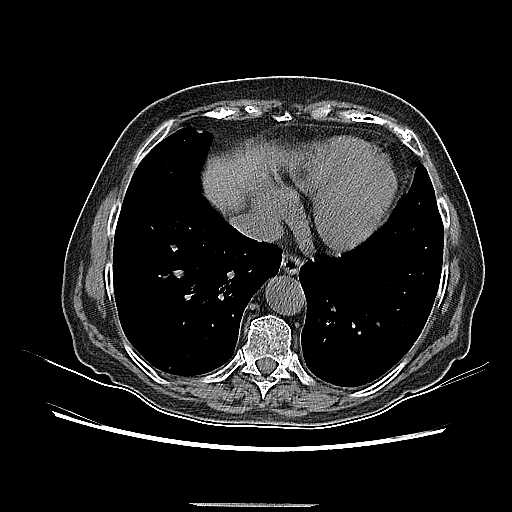

Reconstructed NATIVE CT scan (cycle consistency)

Full window (WL 1023.5, WW 4095 β†’ Low βˆ’1024, High +3071)

Lung window (WL -600, WW 1500 β†’ Low βˆ’1350, High +150)

Mediastinum window (WL 40, WW 400 β†’ Low βˆ’160, High +240)

Original VENOUS CT scan

Generated VENOUS CT scan (A→B translation)